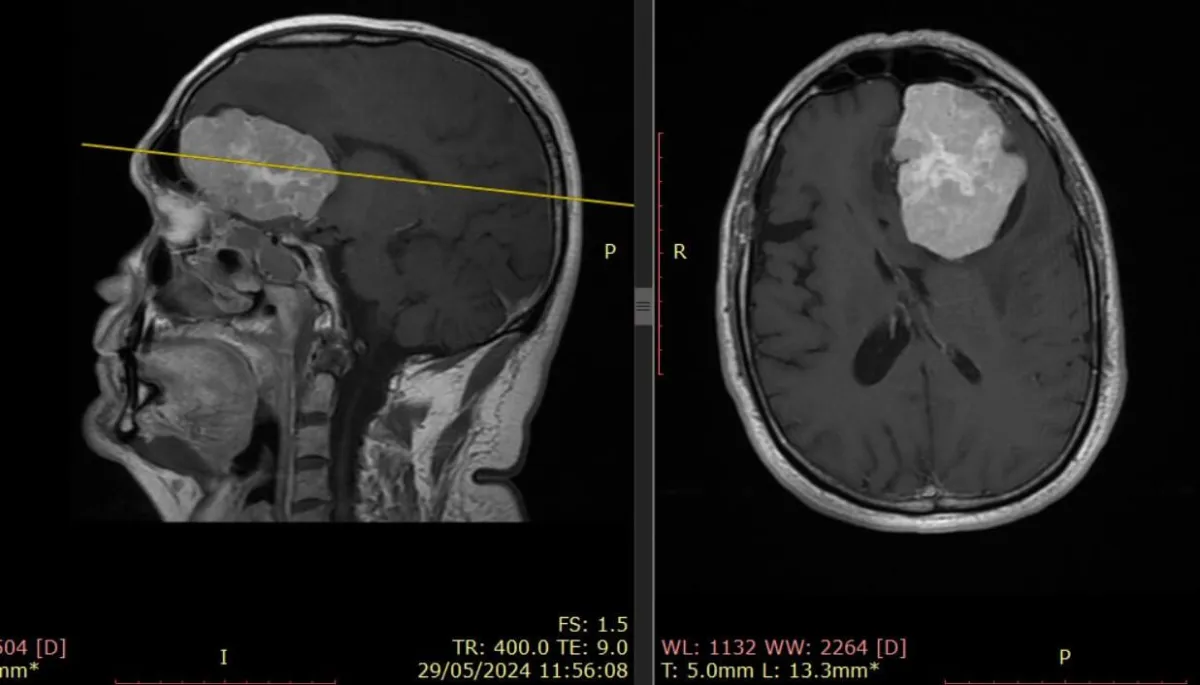

El Dr. Francisco González-Llanos es un neurocirujano reconocido internacionalmente por su dominio en bypass extra-intracraneales, revascularización cerebral compleja y cirugía de base de cráneo.